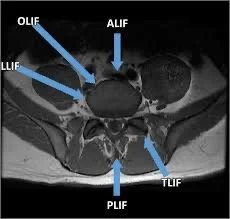

🔹 The Five Main Approaches to Lumbar Fusion

There are five primary surgical approaches to place the interbody spacer. Each has its own advantages and considerations, and your surgeon will choose the one that best fits your condition and anatomy.